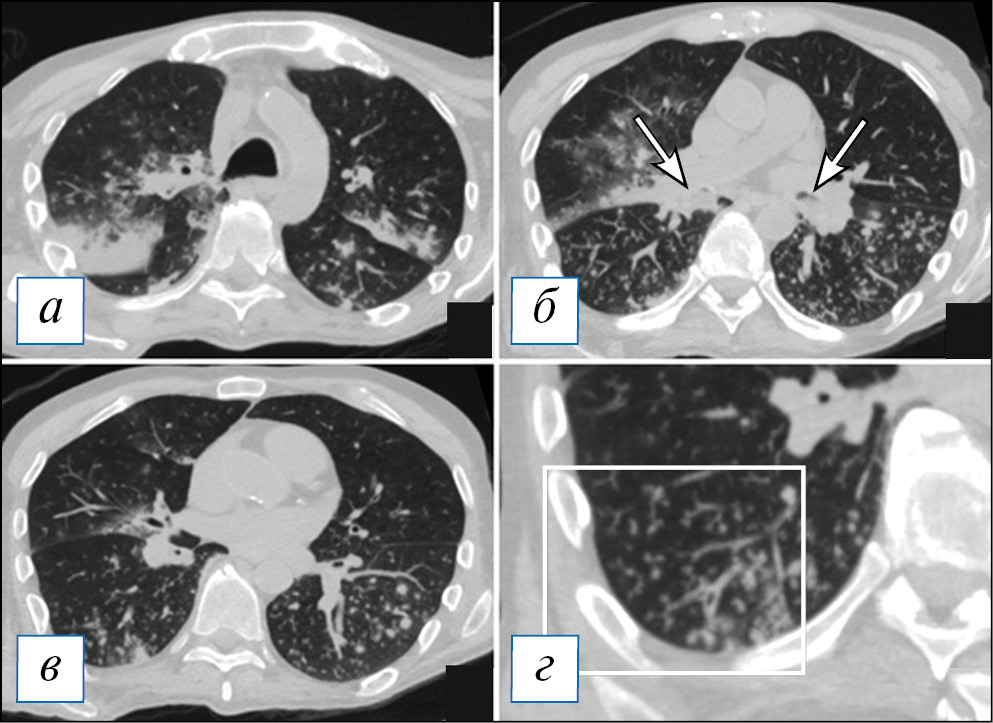

По данным компьютерной томографии (КТ) у пациентов с очаговой пневмонией обнаруживают небольшие перибронхиальные очаги, обычно солидного типа или с нечеткими контурами за счет ободка «матового стекла», при бронхиолите — мелкие очажки в виде симптома «дерева с набухшими почками», при этом прилежащие стенки бронхов могут быть утолщены и уплотнены за счет воспалительного процесса. Возможно слияние очагов, которое не принимает характера обширной инфильтрации. При пневмонии контуры очагов менее четкие из-за преобладания экссудативного воспалительного компонента, что отличает ее от бронхиолита [38]. Важным симптомом бронхогенного процесса можно рассматривать наличие патологического содержимого в просвете бронхов, что представлено слизистым или гнойным содержимым (рис. 1). На традиционных рентгенограммах изменения из-за малого размера могут быть вовсе не заметны или представлять собой мелкие очаги/ограниченную диссеминацию; отмечается локальное усиление/обогащение легочного рисунка, преобладающее в какой-то одной доли легкого.

Рис. 1. Компьютерная томография органов грудной клетки в аксиальной проекции (а–г). Двусторонняя сливная бронхопневмония и бронхиолит у пациента с наличием в мокроте S. pneumoniae и S. aureus в значимых титрах. С обеих сторон, больше в нижних долях, на фоне обтурации просветов крупных бронхов патологическим содержимым (стрелки) имеются перибронхиальные разнокалиберные очаги, в том числе по типу симптома «дерева с набухшими почками» (рамка). В верхних отделах данные очаги сливаются в инфильтраты. [Изображения из архива авторов]. / Fig. 1. Chest CT, axial projection (а–г). Bilateral bronchopneumonia and bronchiolitis (with the etiology of S. pneumoniae and S. aureus confirmed by a sputum test). On both sides, more in the lower lobes against the background of bronchial sputum obturation (arrows), there are peribronchial nodules of various sizes, including a “tree in bud” sign (frame). In the upper lungs areas the nodules formed infiltrates. [Images from the authors’ archive].